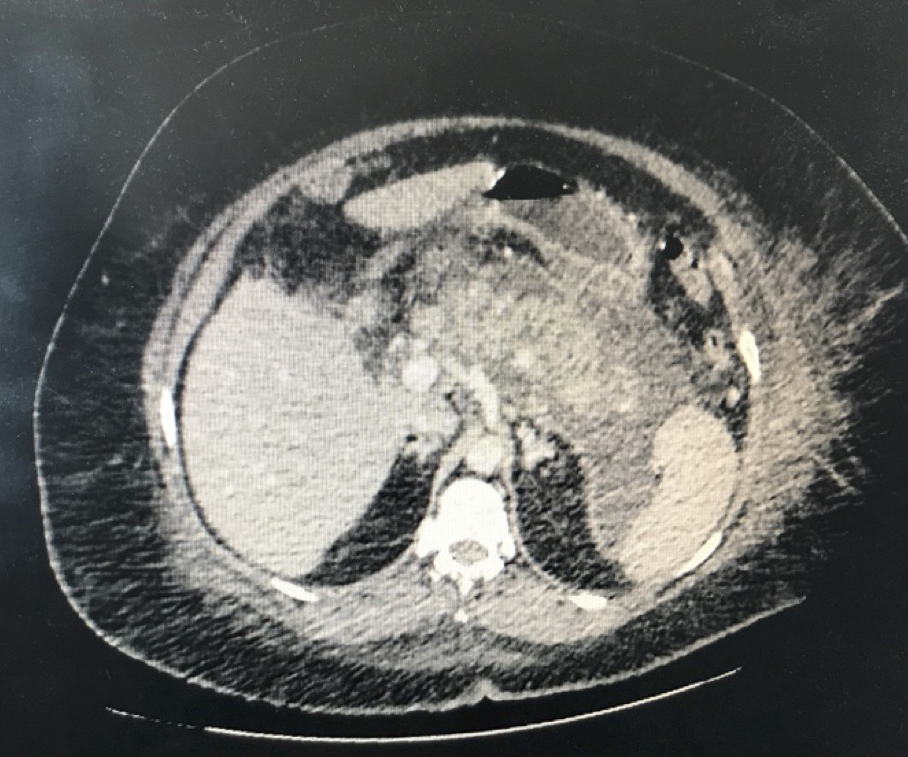

La douleur de la pancréatite est épigastrique irradiant dans le dos, majorée par la respiration profonde et la position antalgique est en chien de fusil.